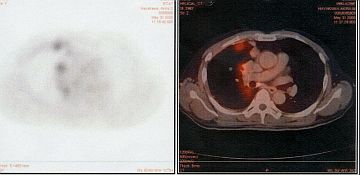

中皮腫は体腔の内面を広く覆う漿膜に発生する腫瘍で、胸膜・腹膜・心膜および極めて稀に精巣鞘膜から発生します。最も多いのが胸膜に発生する中皮腫です。

胸膜中皮腫は予後の芳しくない悪性腫瘍ですが、早期例であれば、ミカンの“房の皮”を剥ぐ手術(胸膜剥皮術)や、ミカンの実を根こそぎ切除する手術(胸膜肺全摘術)を行うことがあります。